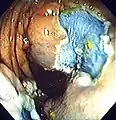

Colonoscopy (/ˌkɒləˈnɒskəpi/) or coloscopy (/kəˈlɒskəpi/)[1] is a medical procedure involving the endoscopic examination of the large bowel (colon) and the distal portion of the small bowel. This examination is performed using either a CCD camera or a fiber optic camera, which is mounted on a flexible tube and passed through the anus.[2][3]

The purpose of a colonoscopy is to provide a visual diagnosis via inspection of the internal lining of the colon wall, which may include identifying issues such as ulceration or precancerous polyps, and to enable the opportunity for biopsy or the removal of suspected colorectal cancer lesions.[4][5]